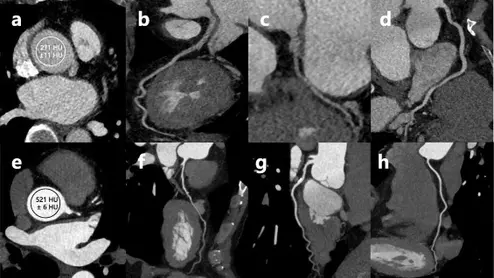

CCTA with patient-specific versus fixed post-trigger delay

New research compares peak enhancement timing of a patient-specific post-trigger delay and a fixed delay during CCTA.